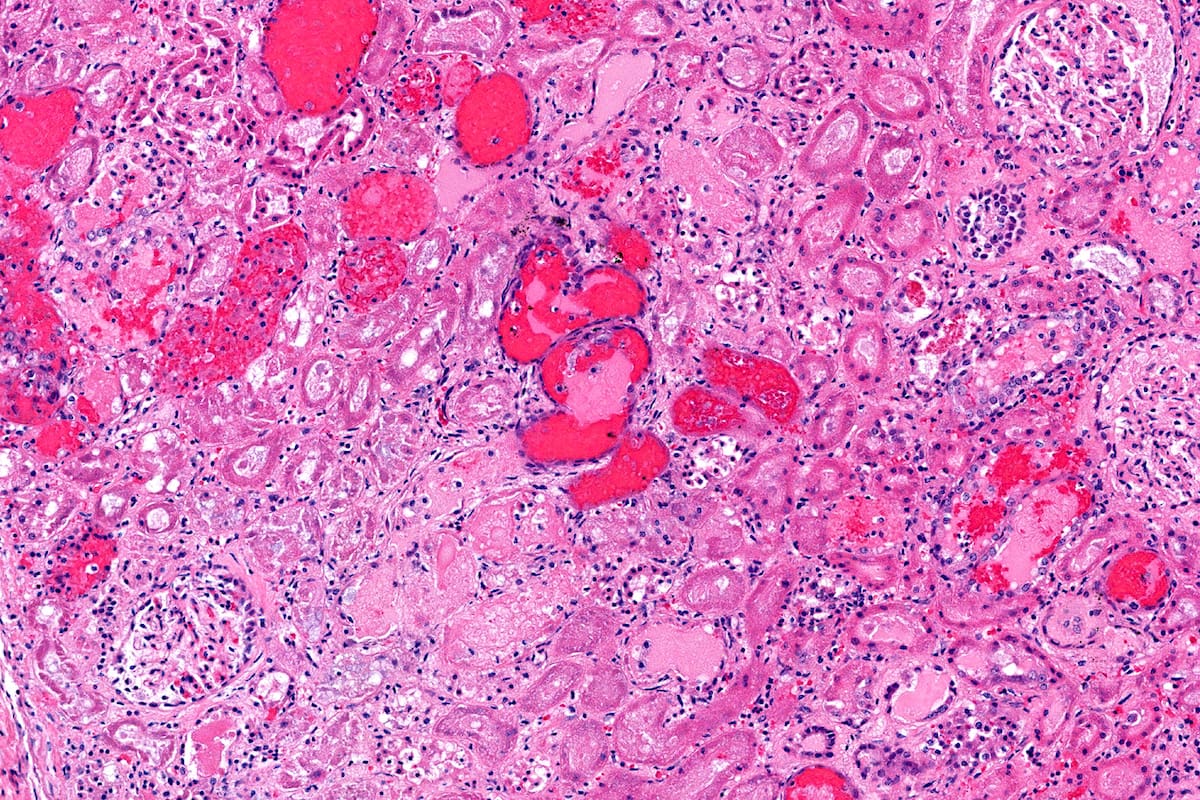

La Argentina registra la mayor incidencia a nivel mundial del Síndrome Urémico Hemolítico (SUH), una enfermedad grave caracterizada por daño agudo de los riñones. Se trata de una afección que preocupa especialmente a padres de niños menores de cinco años, el grupo de mayor riesgo, ya que actualmente no cuenta con un tratamiento específico. Por ello, la prevención se convierte en la herramienta especial para combatirla.

“La bacteria llega, se instala y manda un ‘delivery’ al riñón que es una toxina liberada por la bacteria Escherichia coli), que impacta sobre el riñón y genera insuficiencia renal”, detalló el doctor.